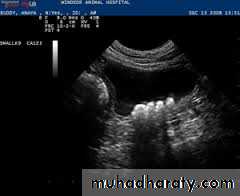

Classification of hydronephrosis in grade I–IV.

• Hydronephrosis grade I: dilatation of the renal pelvis without dilatation of the calices without signs of parenchymal atrophy. • Hydronephrosis grade II: dilatation of the renal pelvis and calices. No signs of parenchymal atrophy. • Hydronephrosis grade III: Minor signs of organ atrophy present (flat papillae and blunt fornices).• Hydronephrosis grade IV: massive dilatation of the renal pelvis and calices. Significant signs of renal atrophy (thin parenchyma).